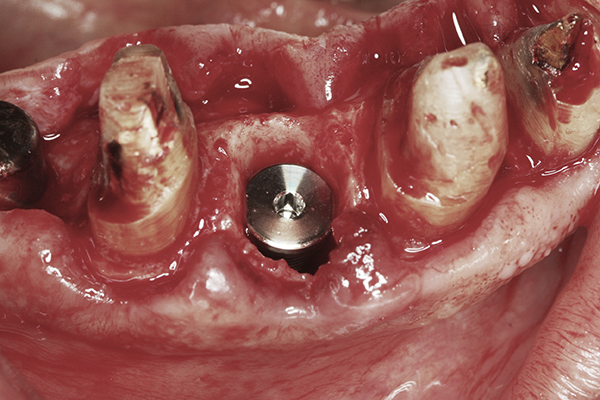

Fig 4. Clinical view of an implant placed into an immediate extraction socket at site No. 28. A n insertion torque of <10 Ncm resulted in a spinner.

Figure 4

Apparently with time, stable implants placed with low initial torque develop bone characteristics around them that are similar to sites where implants were placed with a high initial torque (Figure 4 and Figure 5). Conversely, for implants placed with a high initial torque, the healing process, despite the high initial torque, provides a level of biologic stability that is not necessarily influenced by the initial insertion torque value.